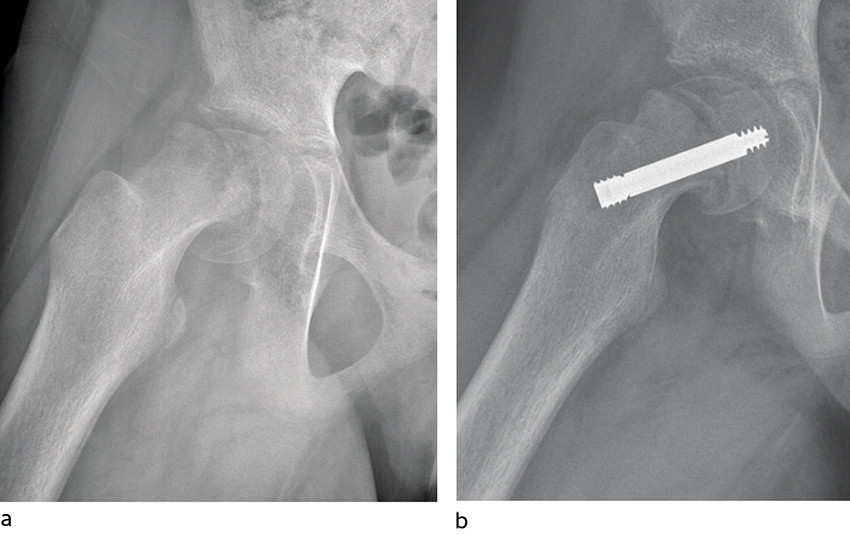

Ved epifysiolysis capitis femoris, epifysiolyse av lårbenshodet, skjer det en glidning i vekstskiven (epifyseskiven) mellom lårbenshodet (epifysen) og lårhalsen (metafysen) øverst i lårbenet (figur 1, figur 2). Gjennomsnittsalderen ved diagnose er 12 år for jenter og 13 år for gutter. Tilstanden forekommer utelukkende så lenge epifyseskiven er åpen, og meget sjeldent ved alder under 9 år og over 16 år. Om lag 25 % får glidning i begge hoftene.

Standard behandling er operativ stabilisering av epifyseskiven. Hensikten er å gjøre pasienten symptomfri samt hindre ytterligere glidning. Epifyseskiven stabiliseres in situ, det vil si man gjør ingen forsøk på å reponere glidningen. Imidlertid vil en del av feilstillingen kunne reponere seg spontant ved ustabil epifysiolysis capitis femoris i forbindelse med leiring under operasjon (figur 2). Grunnen til at det ikke skal gjøres noe aktivt forsøk på reponering er at det gir økt risiko for skade på blodforsyningen til epifysen, med fare for caputnekrose som komplikasjon (11).